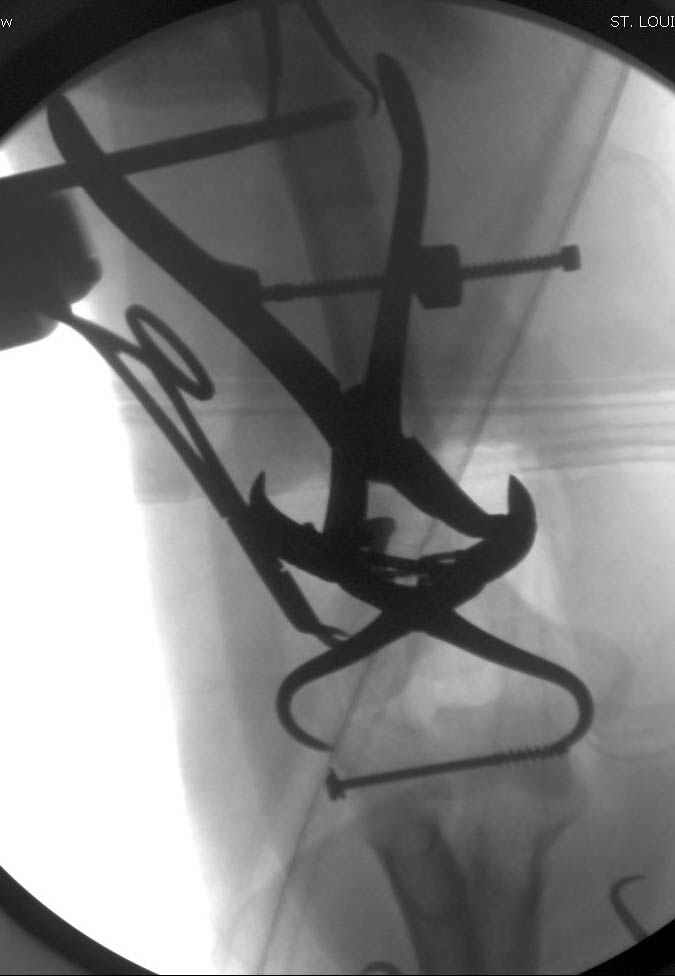

На шестой день сделали открытую репозицию чрезлоктевым доступом двумя locking plate, локтевой нерв был ушибленным, после операции положительная динамика в Flexor Carpi Ulnaris. Фиксацию локтевого отростка произвели tension band technique с дополнительным шурупом.

Этапы операции на снимках....